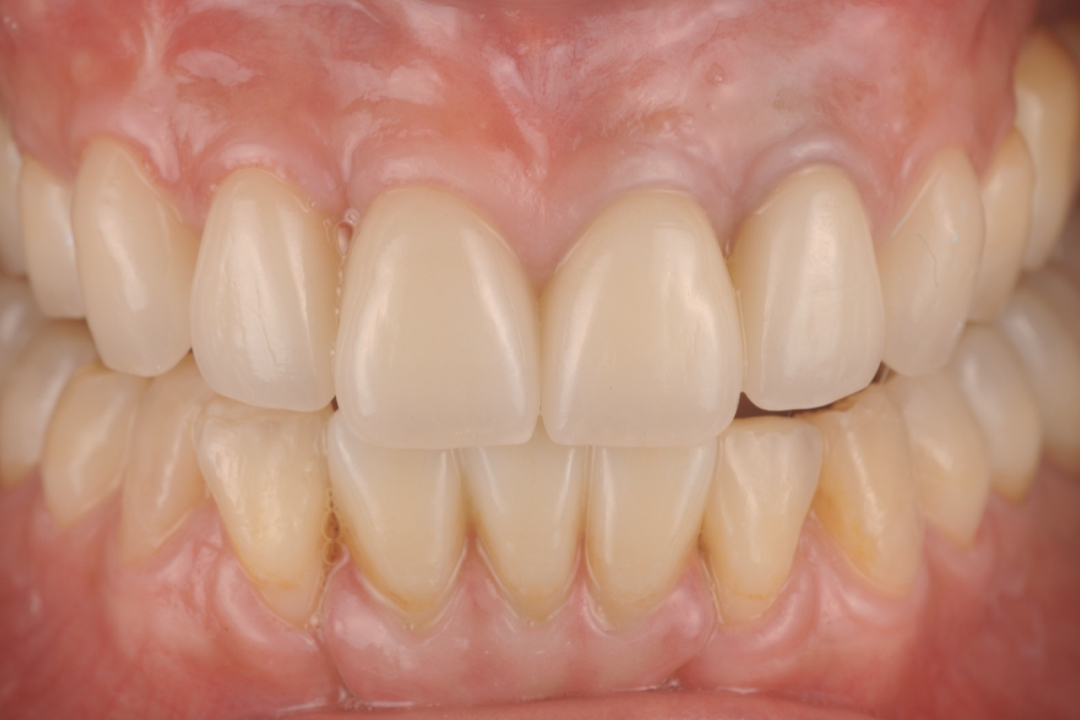

上唇の腫脹を認め、CT検査にて根尖部に嚢胞様透過像を認めた。左上の前歯が不自然に大きく噛み合わせが強くなっていたことがフレアアップの一因と考える。精密根管治療を行い、感染経路を遮断したのち歯根端切除術にて嚢胞を摘出した。

治療後

歯の保存、嚢胞の摘出、審美的改善